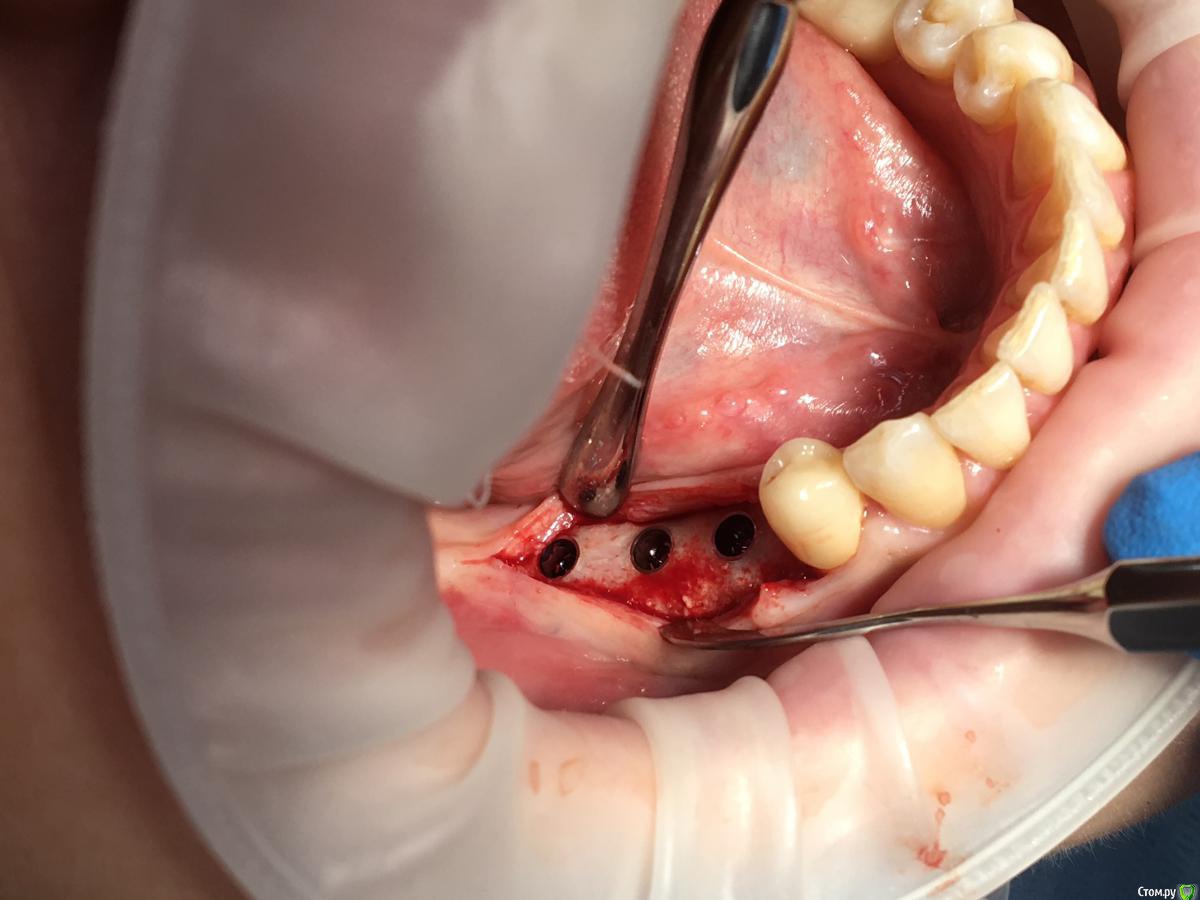

Shakirbura Опубликовано 8 ноября, 2017 Поделиться Опубликовано 8 ноября, 2017 Здравствуйте, коллеги!Раскрыл через 5 месяцев после нкр. Поверхностный слой материала легко соскреб распатором. Глубоко ковырять не стал. Был апатос микс + ауто 60/40. Почему такая картина, кто может подсказать?Есть надежда, что это станет костью? Ссылка на комментарий

Shakirbura Опубликовано 9 ноября, 2017 Автор Поделиться Опубликовано 9 ноября, 2017 Скорее всего недостаточная иммобилизация графтаТри тентовых винта и пять фиксирующих было. Ссылка на комментарий

Shakirbura Опубликовано 9 ноября, 2017 Автор Поделиться Опубликовано 9 ноября, 2017 думаю запитки от периоста было не достаточно, лямина мощный барер , хотя у меня было один раз что при раскрытии она полностью биодеградировала.я бы еще месяца 4 подождал.Я убрал мембрану и поставил импланты, там было во что зафиксировать, теперь буду ждать. Ссылка на комментарий

Shakirbura Опубликовано 4 мая, 2018 Автор Поделиться Опубликовано 4 мая, 2018 Закончу кейс, раз уж начал...Оставил импланты на 4 месяца.Провел смещение лоскута, а через месяц раскрыл с ФДМ и ССТ.Вот что получилось. Всем спасибо. 7 Ссылка на комментарий